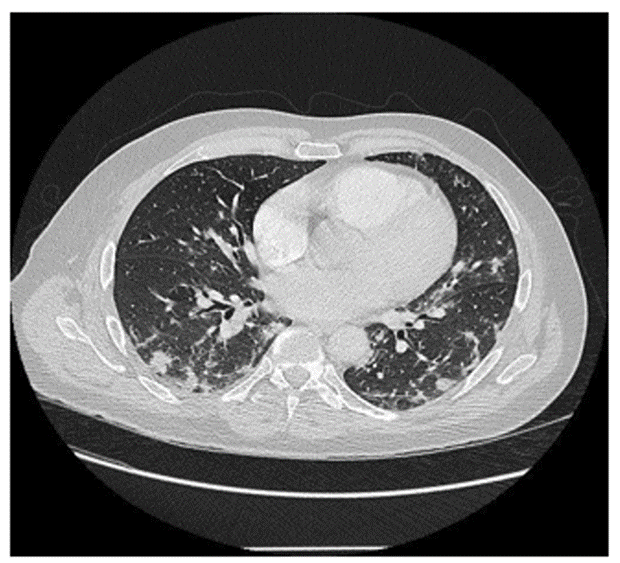

On September 03, 2021, a 56-year-old man was admitted in infectious diseases department for a moderate Covid-19 infection. He did not show previous diseases, was not a smoker and had a Body Mass Index of 29. He had no significant medical history. Symptoms had begun 10 days before admission. They consisted in fever (39°C), chills, anosmia, agueusia, asthenia and weight loss (5 kg). The first specific Polymerase Chain Reaction (PCR), done on 03/12/2021, was positive with English variant. C-Reactive Protein (CRP) test was high (185 mg/L), arterial gasometry showed before H2 therapy a significant hypoxemia with adjunction of 4L/min O2 by nasal canula (pO2: 8,41 kPa with normal values (NV): 9,50-13,30; pCO2: 4,98 kPa with NV: 4,70-6,10, pH: 7,44 with NV : 7,37-7,45 and bicarbonates : 24,5 mmol/L with normal values : 21,0-26,0). CT lung imaging is shown in Figure 1.

Concerning thoracic auscultation, crackles were found on both sides of the lung. The respiratory frequency was about 30 cycles per minute. Concerning chest X ray, performed on the day of admission, it showed multiple opacities, with infiltration confirmed by CT scan on the same day, which also highlighted extension of infiltrates to 50%, which suggests a severe pulmonary disease, as represented in Figure 2.